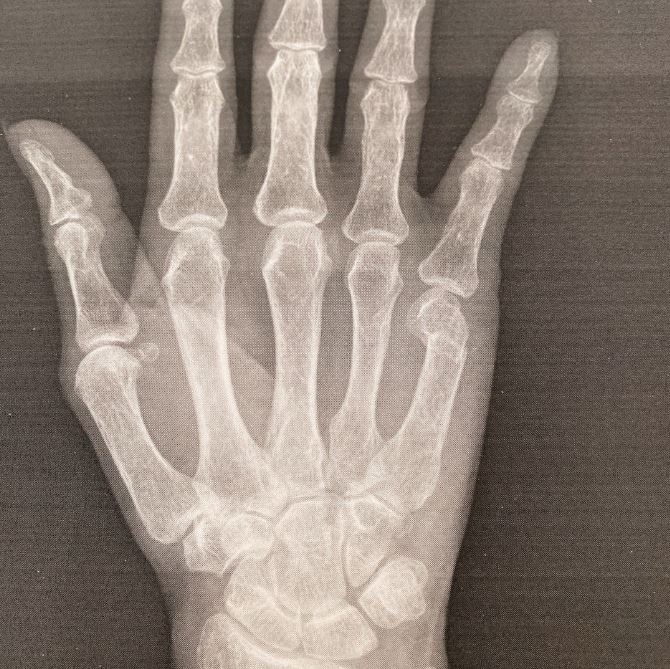

ブログには、整形外科を受診したときのことが記されていて、「昨日受診した○○整形外科の院長先生の治療には感動しました‼️」と書き出し「小指 第3関節の下 綺麗に折れてるのが 分かりますよね」「折れた骨が 内側に入り込んでるのが分かります」と骨折した指のレントゲン写真とともに説明。

そして「びっくり‼️真っ直ぐになってるーーー」「きゃーっ‼️‼️‼️驚きましたーーー‼️‼️‼真っ直ぐになってるーーー」と驚きの様子を綴っています。